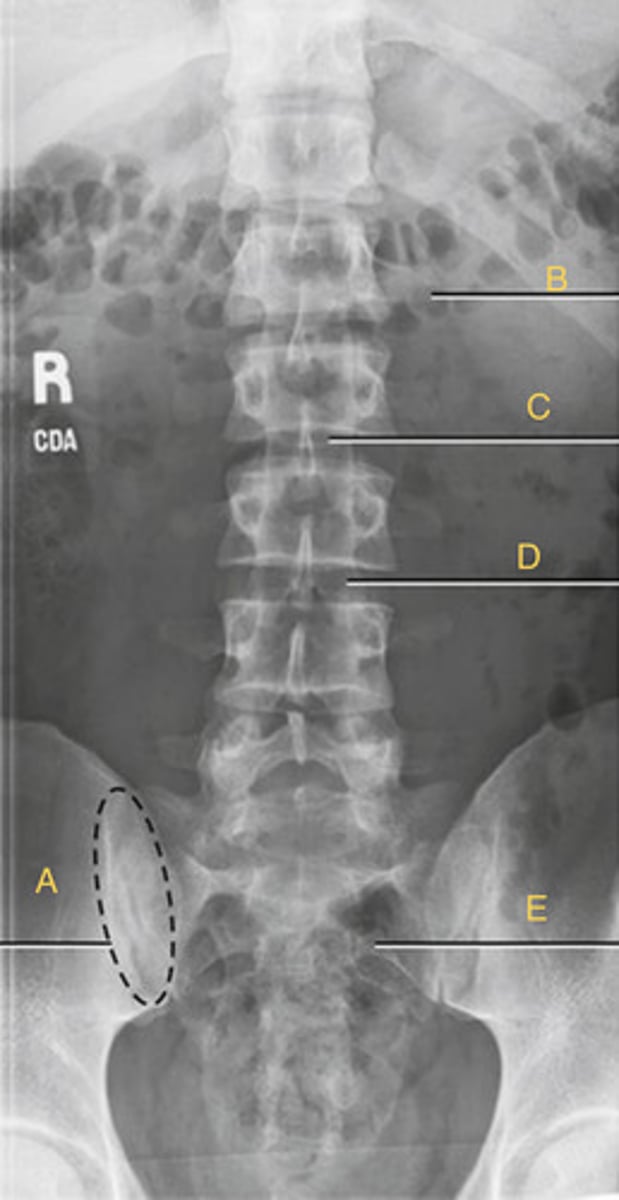

L2 Transverse process

A.

L3 Pedicle

B.

L3 pars interarticularis

C.

L3 inferior articular process

D.

L4 Superior articular process

E.

L3-4 zygapophyseal joint

F.

Oblique lumbar

What position?